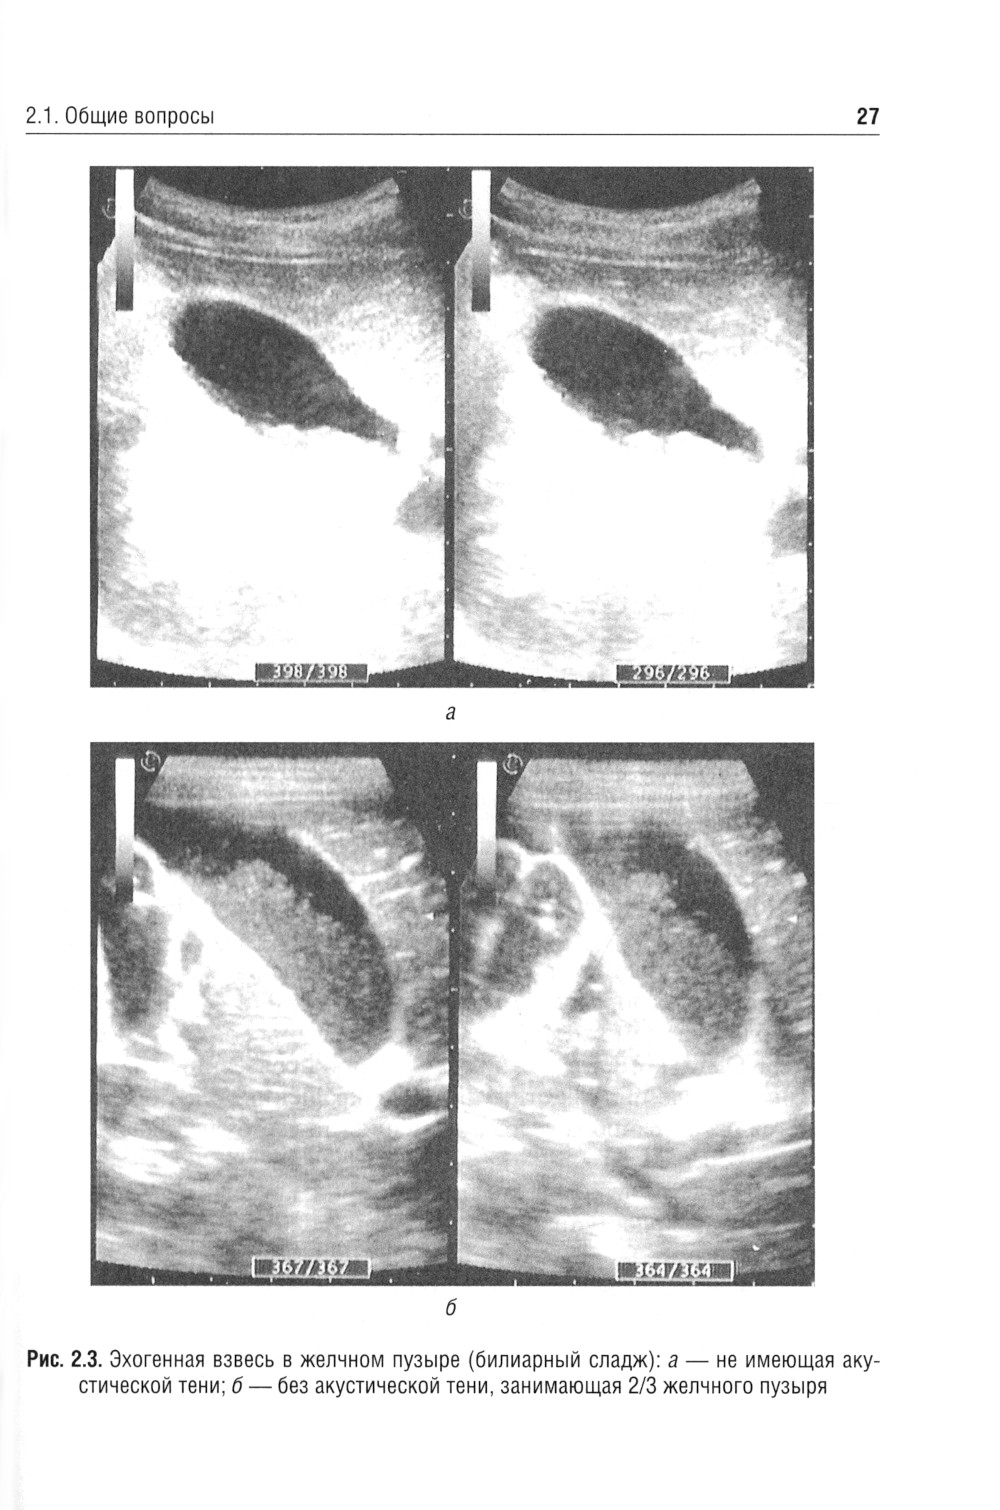

В учебном пособии рассмотрены отдельные морфофункциональные особенности билиарного тракта, вопросы физиологии желчеобразования и желчеотделения, а также представлены материалы, касающиеся диагностики и лечебной тактики дискинезий желчевыводящих путей, хронического холецистита и желчнокаменной болезни. Приведены анамнестические, клинические и дополнительные критерии диагностики, позволяющие оптимизировать диагностическую тактику, а также программы назначения лечебно-коррекционных мероприятий с учетом индивидуальных и возрастных особенностей пациента. Отражены сведения, касающиеся новых клинических вариантов течения билиарных дисфункций у детей, - диспластикоассоциированных дискинезий желчевыводящих путей. Пособие предназначено студентам медицинских вузов, а также врачам-педиатрам, гастроэнтерологам, терапевтам, врачам общей практики.| Издательство | ГЭОТАР-Медиа |